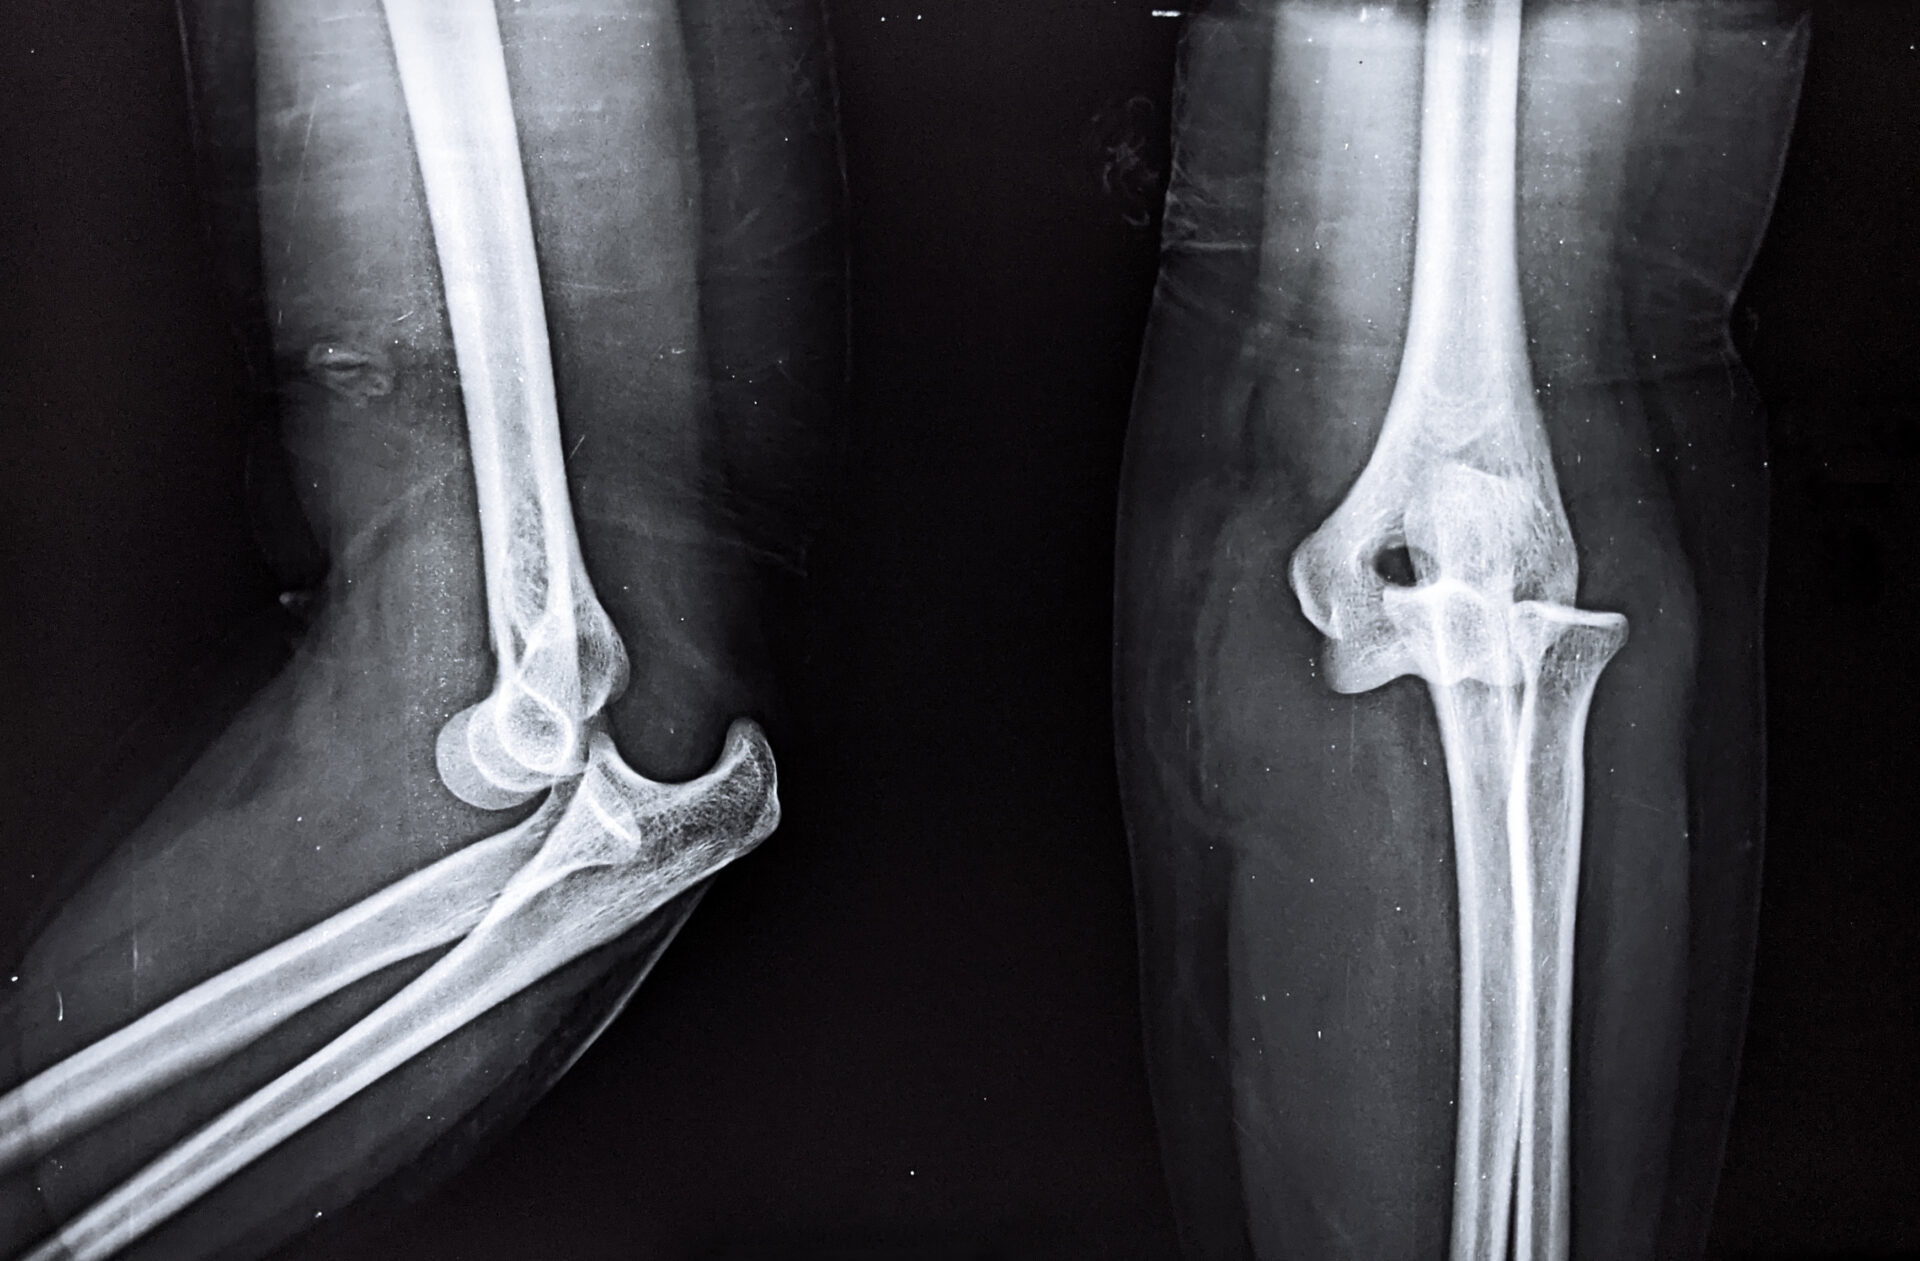

Eine Untersuchung im Krankenhaus ergab dann, dass sie einen Knochenbruch im Bereich der Oberkante der Elle am Unterarm (Olecranon) erlitten hatte. Aus diesem Grund fand ein Eingriff in Form einer „Zuggurtungsosteosynthese“ statt. Während dieser Operation wurde jedoch nicht überprüft, ob der Unterarm der Patientin gedreht werden kann, was notwendig gewesen wäre.

Gut zu wissen: Bei einer „Zuggurtungsosteosynthese“ werden gebrochene Knochen, welche durch Gelenke verlaufen, wieder richtig positioniert und mittels spezieller Drähte befestigt.

Da es bei der hier vorgenommenen Operation immer wieder zu Komplikationen kommen kann, muss gerade am Ellbogen streng darauf geachtet werden, dass die Spitzen der eingesetzten Drähte nicht die Drehbewegung des Unterarmes behindern sowie zu einer Blockade der Speiche führen.

Vorgenommene Untersuchungen ergeben jedoch, dass die Drähte schräg eingebracht wurden und über dem Unterarmknochen hinausstanden. Der eine Draht wurde auch derart falsch in den Knochen eingesetzt, dass es zu einer Blockade zwischen der Speiche und Elle kam. Dadurch war es der Patientin nicht möglich ihren Unterarm zu drehen und es kam zu einer blockierten Unterarmstellung.

Laut dem OP-Bericht wurde nämlich nicht überprüft, ob die Drehbewegung des Unterarms möglich war, was jedoch zwingend hätte erfolgen müssen, da das Risiko, dass die Drähte die Speiche beeinträchtigen bei einer solchen OP sehr groß ist. Diese fehlende Überprüfung stellt einen Befunderhebungsfehler dar, der einem Arzt nicht unterlaufen darf.